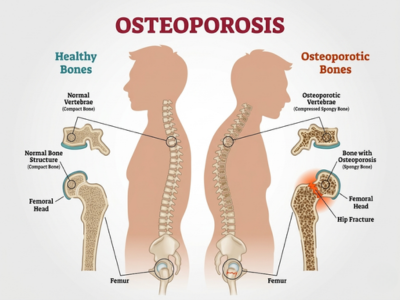

Osteoporosis

Focused care to strengthen bones, prevent fractures, and manage bone density loss through medication and lifestyle changes.

Nutritional Guidance

Diet recommendations to support bone healing, muscle recovery, and overall health.